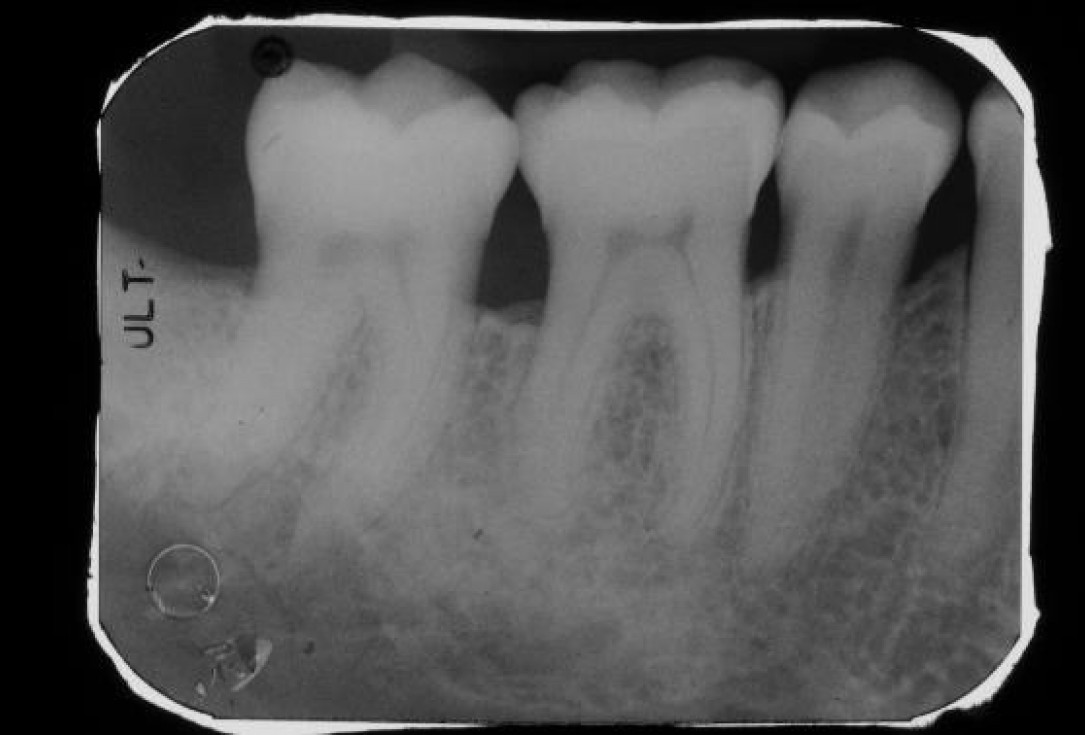

03/22 - Pre-operative radiograph. Deep intrabony defect visible on the distal aspect of tooth 46.

Deep intrabony defects treated using Straumann® Emdogain® - Dr. M. Stefanini